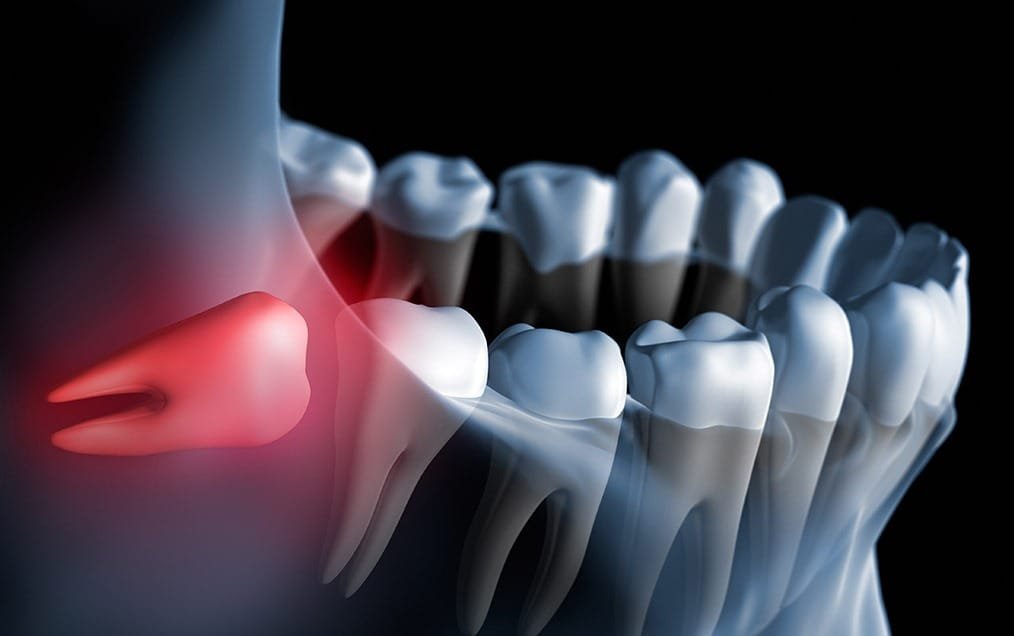

Wisdom teeth can be a source of concern for many people. If there is not enough room in the back of the mouth for wisdom teeth to erupt properly, their growth can be disrupted. For some people, wisdom teeth erupt only partially through the gums, which can result in crowding issues with the surrounding teeth, cavities, gum infections and/or severe pain. Sometimes wisdom teeth can grow in unusual directions, which can cause complications like crowding and damage to adjacent second molars. Impacted wisdom teeth occur when there is not enough room for them to erupt in the mouth and they become stuck under the gums, unable to emerge. When wisdom teeth are impacted in the jaw, this can provide a very fertile ground for bacteria to grow at the opening of the mouth, which can lead to gum infection which could cause considerable discomfort, pain, swelling, and illness. Oftentimes your dentist can foresee future concerns with your situation and may recommend the removal of your wisdom teeth.